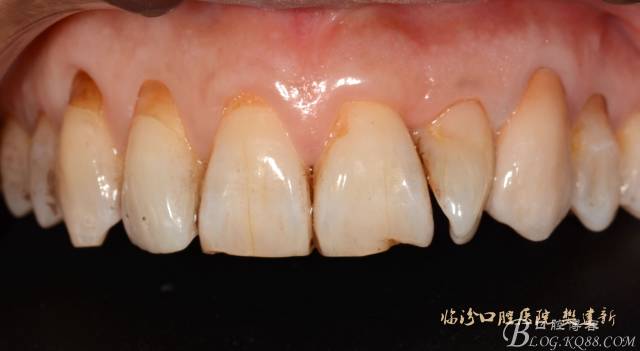

圖4 修復(fù)前選色:

640 (3).jpg